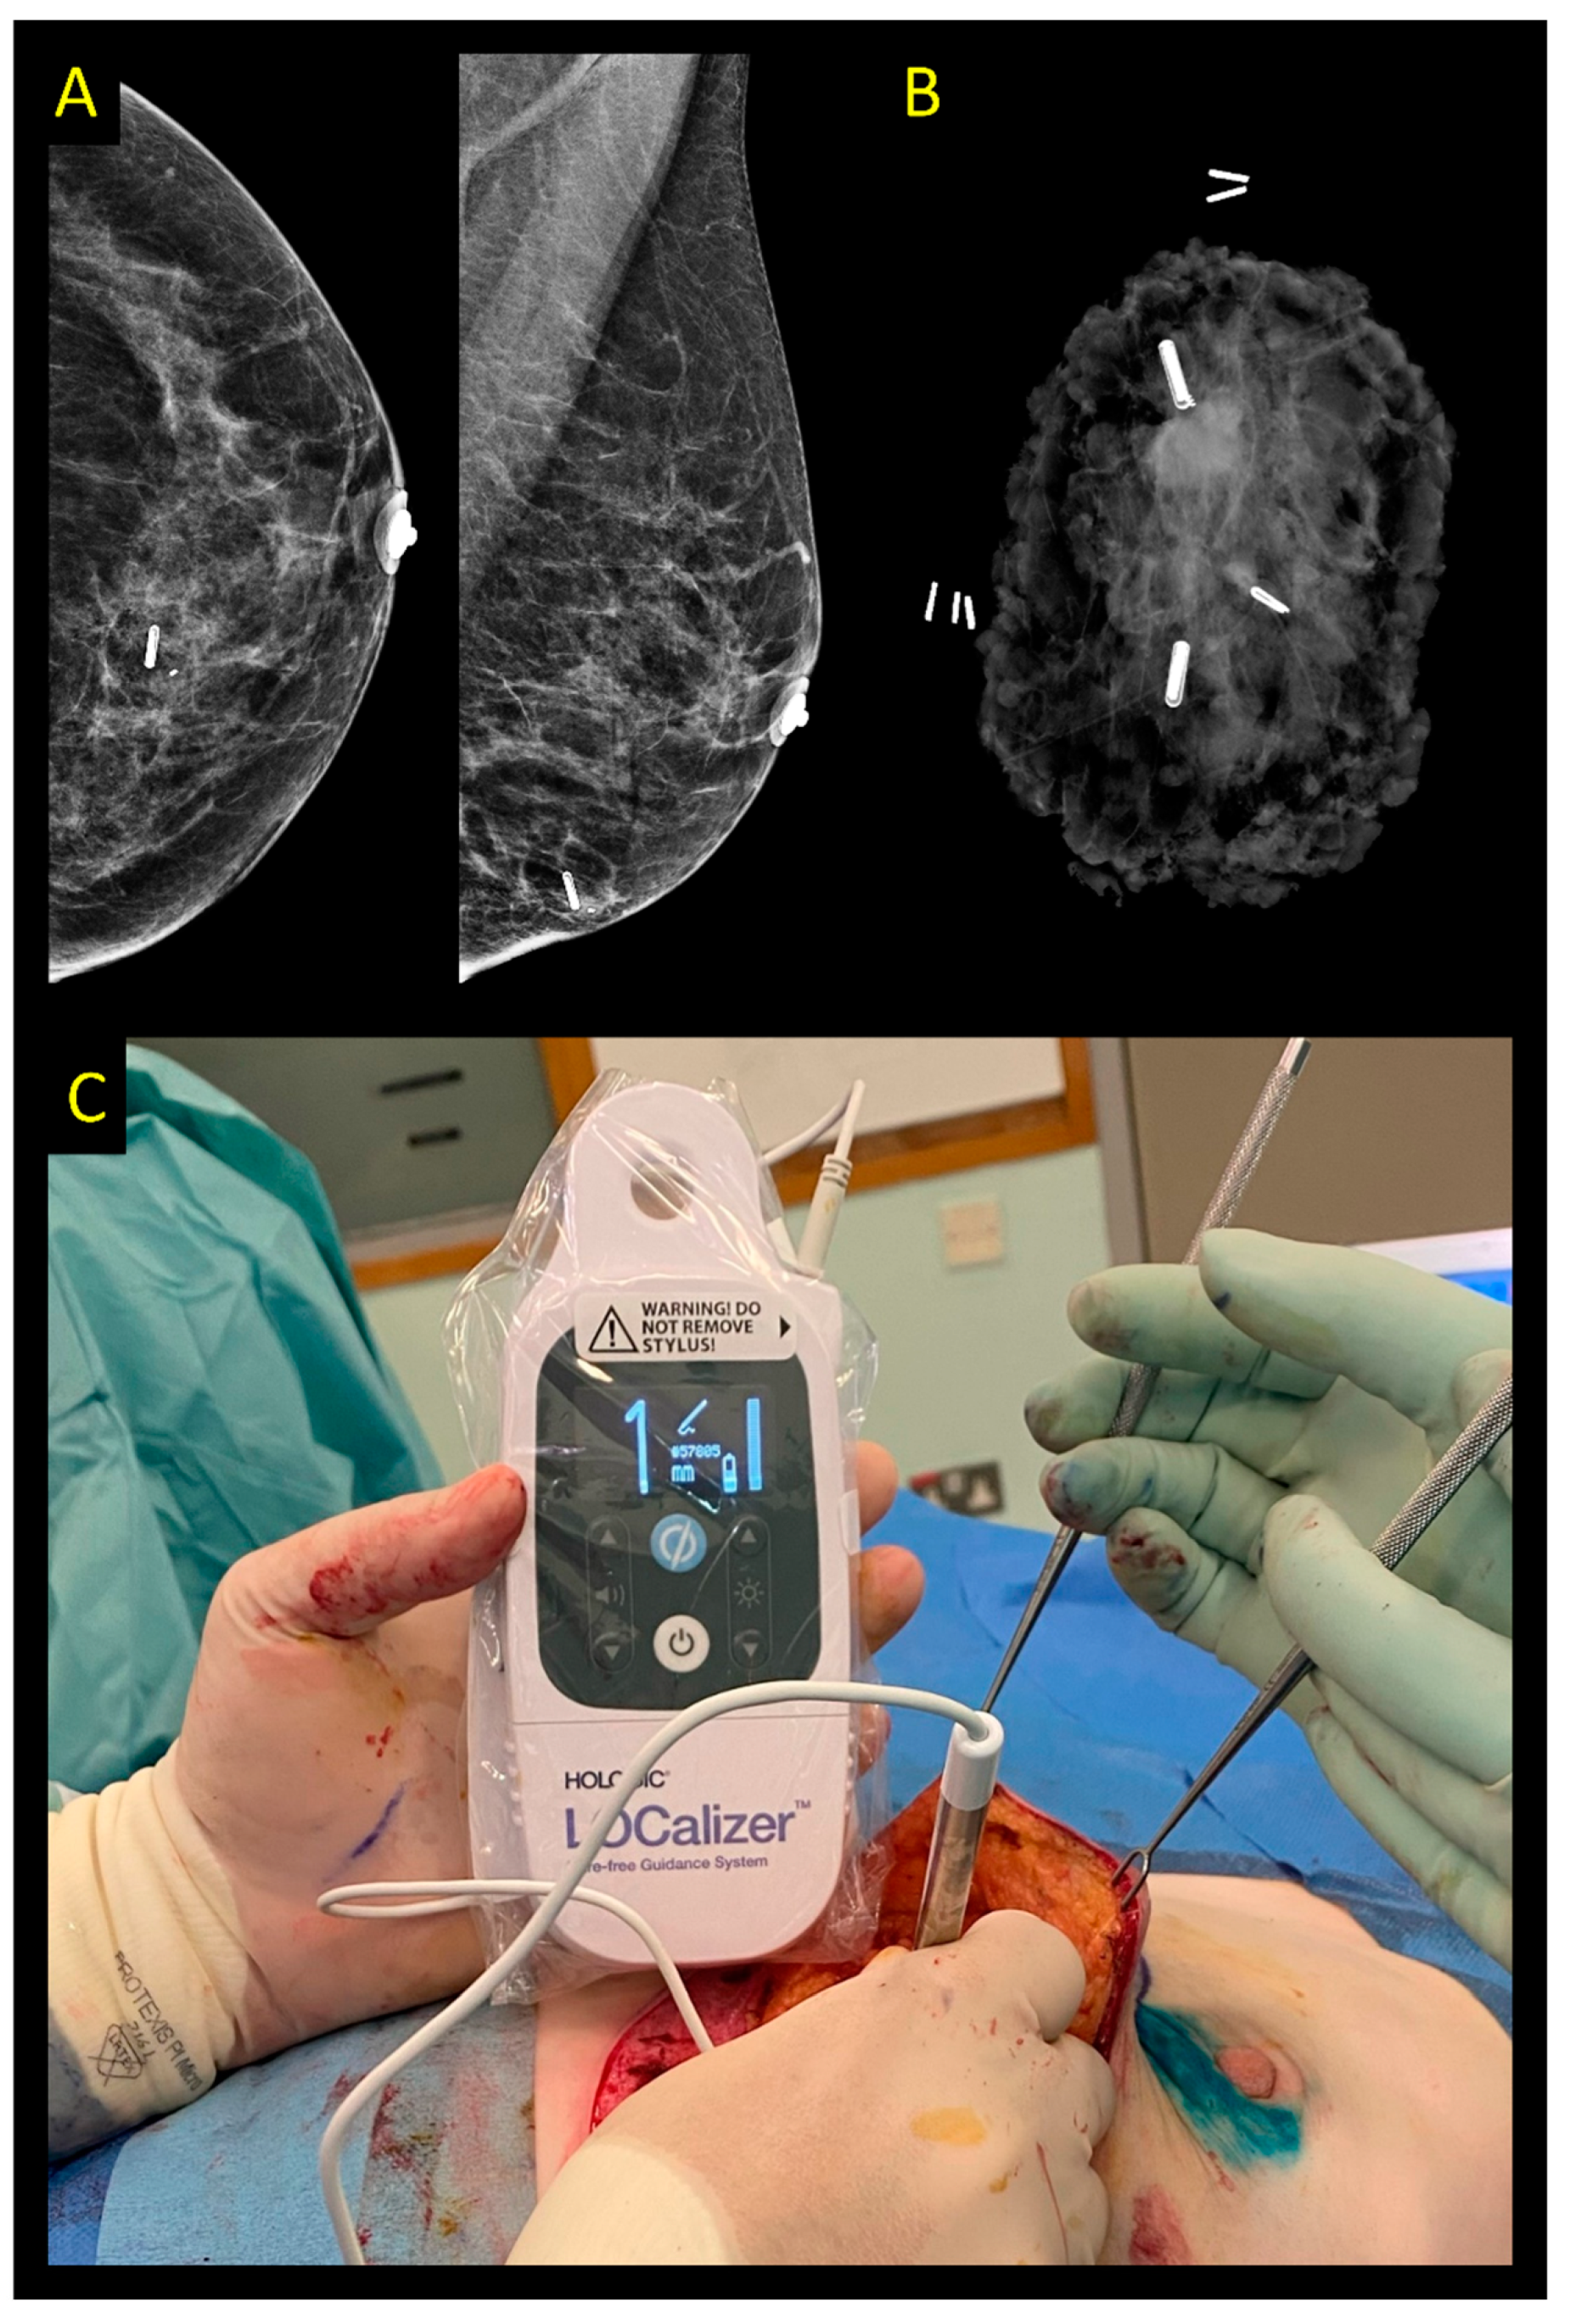

2.3. Magnetic and Paramagnetic Localization

2.6. Radiofrequency Identification Tags